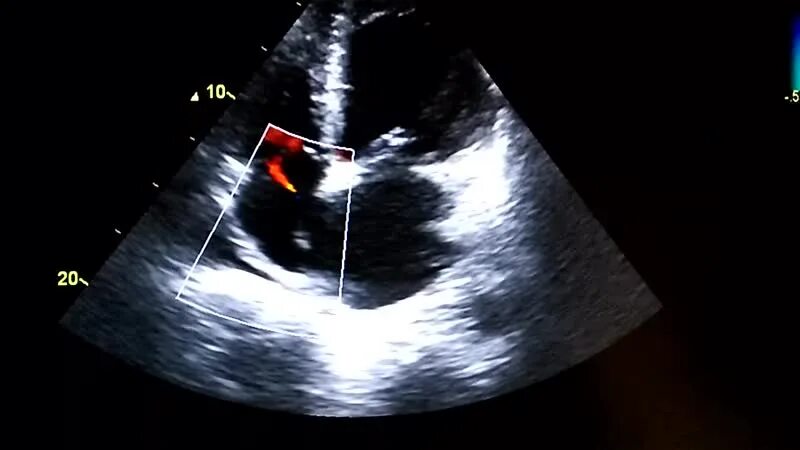

Не закрывается окно у новорожденных